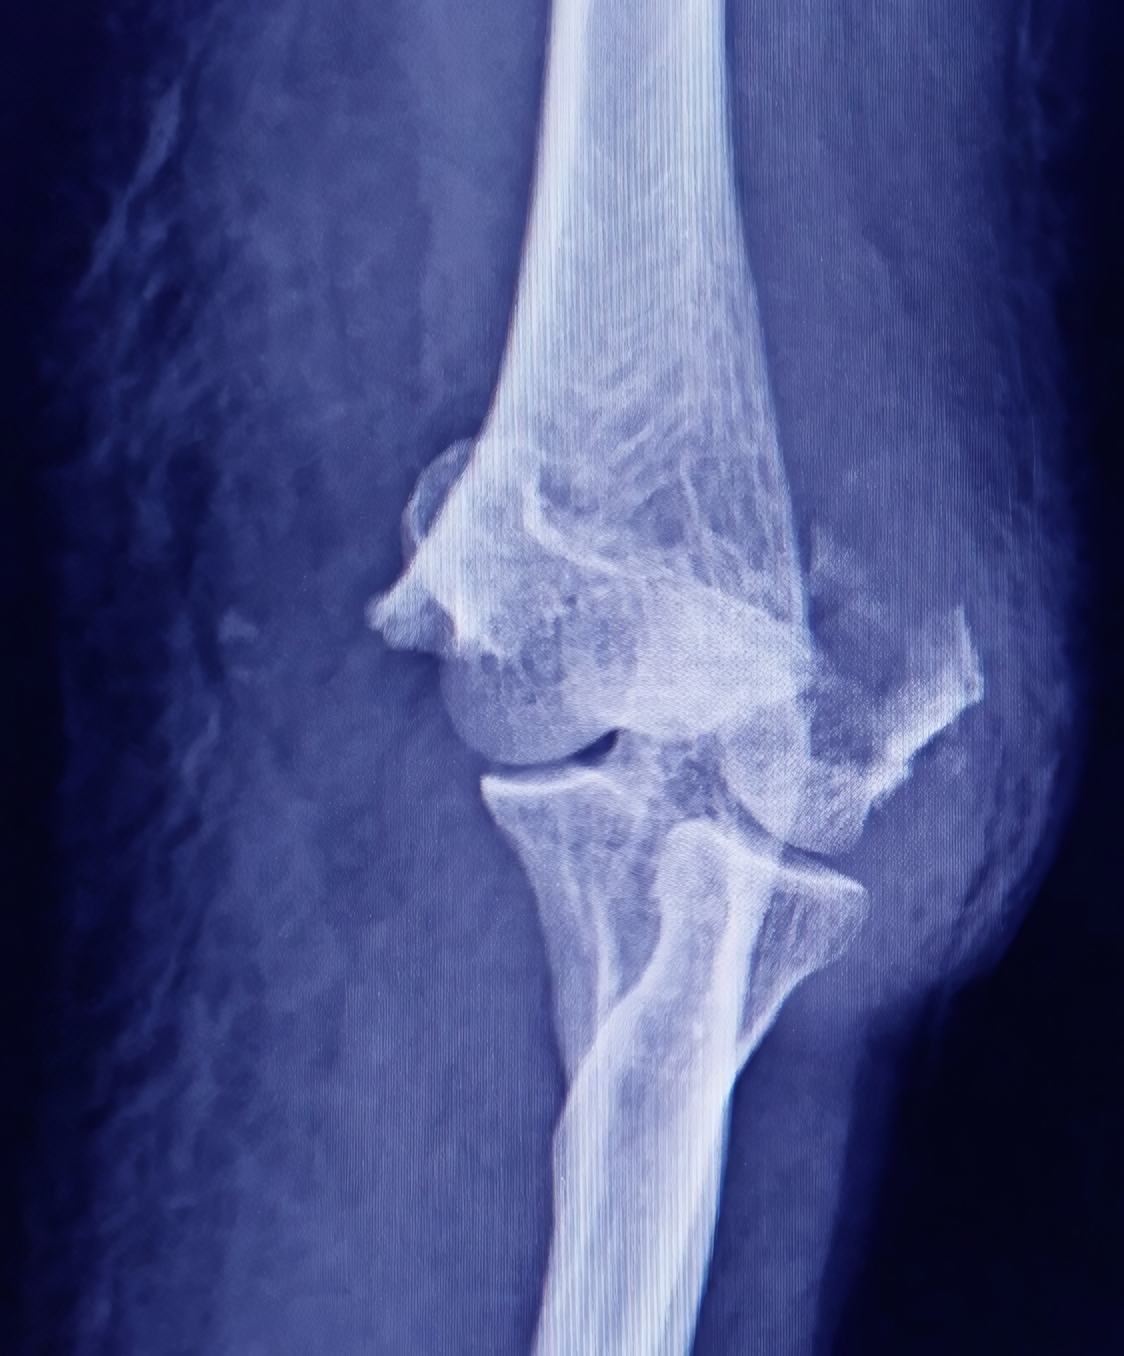

Antes